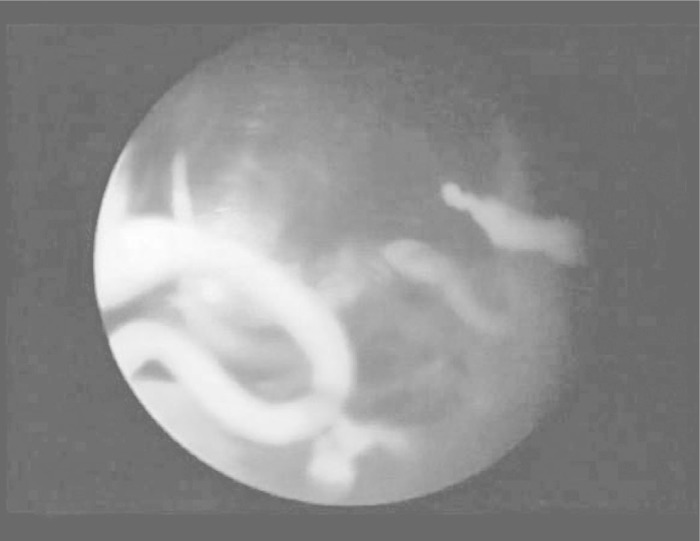

The arthroscopic surgery was performed in lateral decubitus, with posterior, lateral and anterior ports. In the last 35 operations, the anterior port was not used (Figure 7); in these cases, irrigation was provided through the lateral portal, along with instrumentation. It is important to mark out the joint surface of the supraspinatus tendon in the hyperemia zone using monofilament suture (Figure 8), when present, since this may correspond to the calcification area on the bursal surface(4). Complete removal of calcification without causing iatrogenic damage to the affected tendon is fundamental (Figure 9), along with exhaustive irrigation of the subacromial space, because calcium residues (Figure 10) may cause pain after the operation(2). No image intensifier was used during the surgery. The patients were evaluated using the system proposed by the University of California at Los Angeles (UCLA)(17).

Figure 10.

Presence of calcareous granules in the bursal space, seen through posterior port.